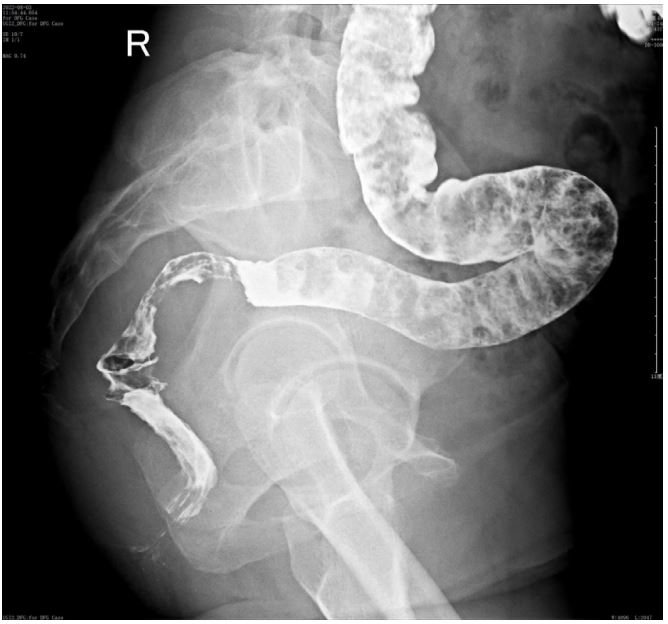

On August 3, 2022 (2-years postoperative), the patient visited the clinic for six months due to anal swelling, the symptoms were not related to menstrual cycle, and a fecal imaging was performed: The distal part of the rectal jug abdomen was seen to be mildly protruding anteriorly during forceful evacuation, with a cystic pouch-like change, about 2.8 cm in length and 0.8 cm in depth. The local intestinal lumen of the sigmoid colon was slightly narrowed, with an upper and lower range of about 3.3 cm, and the margin. The lumen of the sigmoid colon was slightly narrowed, with an upper and lower range of about 3.3 cm, and the margin was not well defined See Figure 1. The intestinal lumen was slightly narrowed, and the endoscope could barely pass through.

Figure 1: Defecography image.